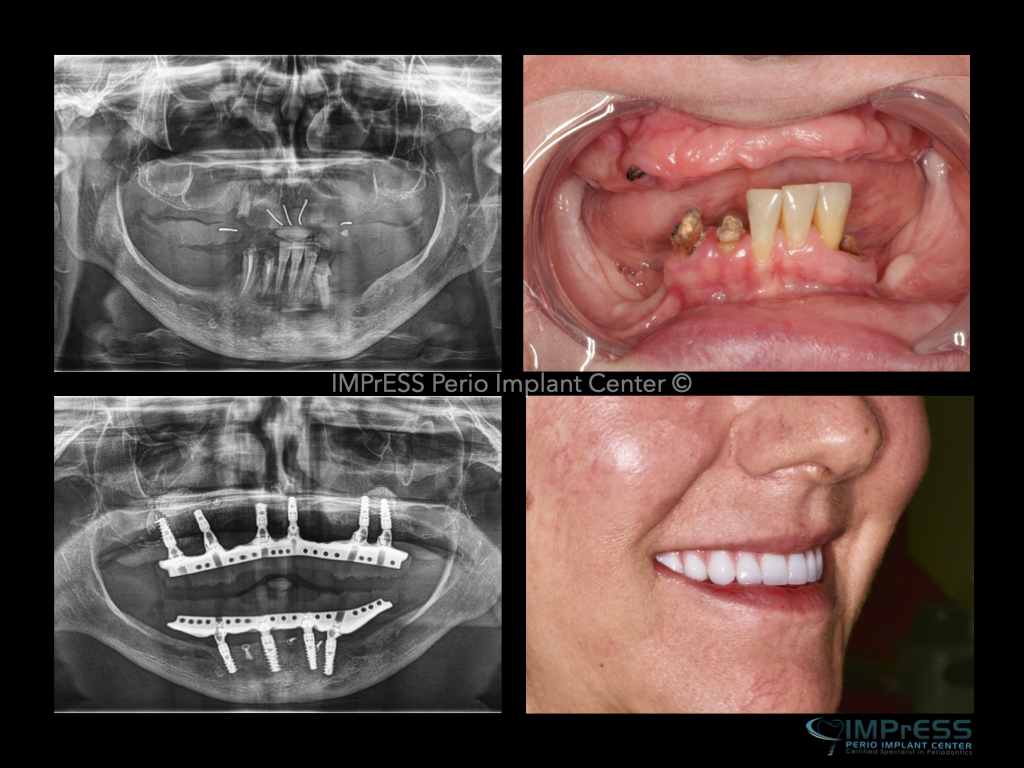

All on X implant Full Mouth Implant Reconstruction All on 4 Implants IMPrESS Perio Implant Center Vancouver Burnaby Periodontist Prosthodontist Implant Specialist Dr. Noroozi Periodontist Implant Specialist

All on 4 All on 6 implants Teeth in a day Full Implant Denture IMPrESS Perio Implant Center Dr. Noroozi Vancouver Implant Specialist

All On X Full Mouth Implants Fixed Teeth IMPrESS Perio Implant Centre Dr Noroozi Burnaby Vancouver BC

Teeth in one day full mouth dental implants Implant teeth impress perio implant center Dr. Noroozi

Step 2: For a permanently anchored dental implant bridge, several dental implants are installed to form a good foundation. Because the dental implants are anchored in the jawbone, they stimulate the bone tissue and help to maintain healthy bone levels and facial structure

Step 3: The abutments are attached to the dental implants and the bridge is fitted in place. All dental work is performed according to your prerequisites and wishes.

Step 4: The dental implant bridge is now in place. It looks and functions like normal teeth. You can now eat whatever you like and laugh without having to worry about the prosthesis falling out.